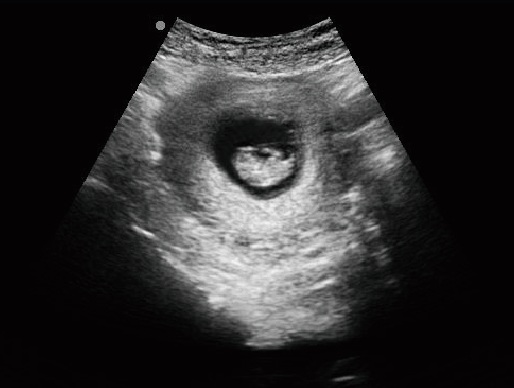

MU15便攜筆記本式獸用B超機

動物寵物超聲診斷儀

·顯示模式:B、B+B、4B、B+M、M、PW

·具有專業的動物產科軟件包,分別是狗、貓、馬、牛、羊

·適用于各種動物的臨床腹部、胸腔,心臟、肌腱、小器官、眼球、生殖系統等的檢查